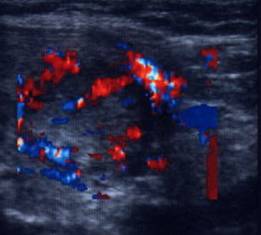

ecocolordoppler si powerdoppler- acelasi nodul

Vascularizatie interna, mai evidenta in powerdoppler.

Acelasi caz. La doppler color - vascularizatie interna, mai evidenta in powerdoppler.